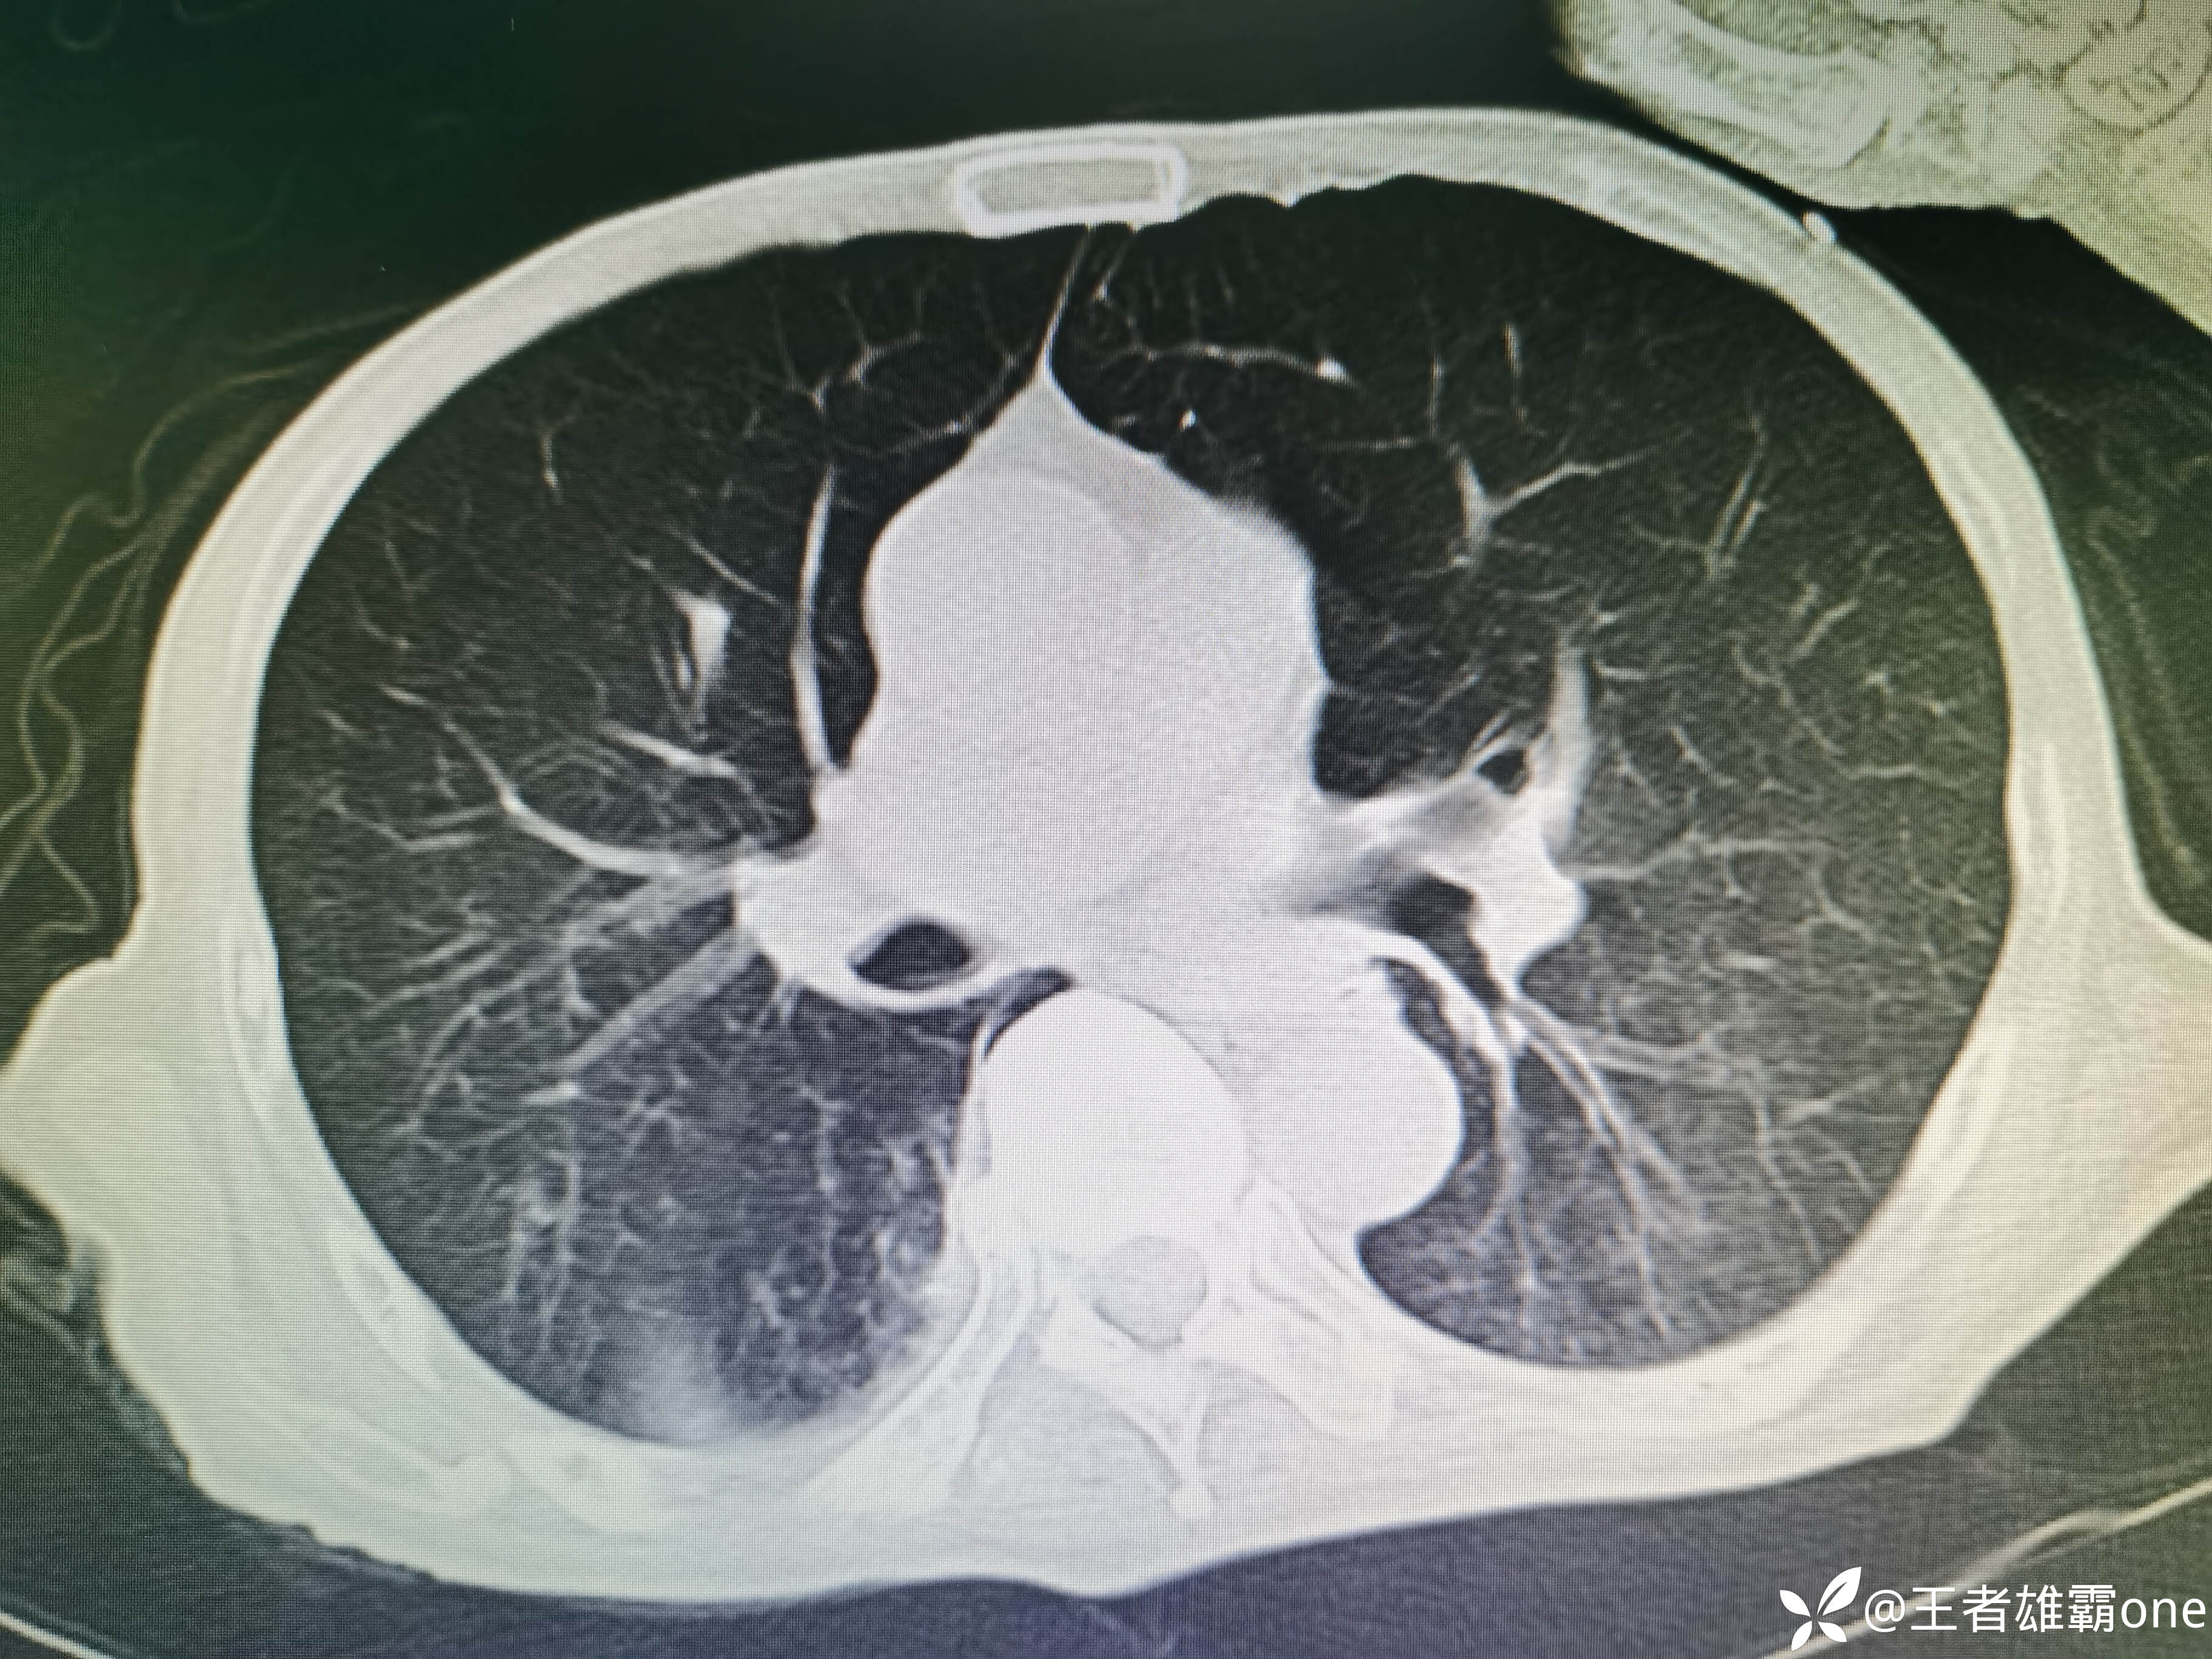

入院时胸部CT:

具体图片: